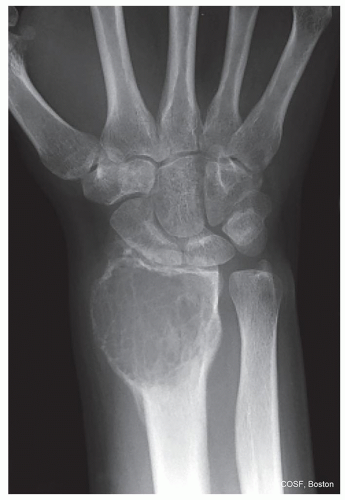

How is the bone responding to the tumor: margination, periosteal reaction? (Figures 41.1,41.2,41.3,41.4,41.5,41.6,41.7,41.8,41.9)

Epiphysis: chondroblastoma in skeletally mature, giant cell tumor in adult (see Figures 41.2 and 41.8)

Metaphysis: Benign—nonossifying fibroma, osteochondroma, unicameral bone cyst, aneurysmal bone cyst, chondromyxoid fibroma (see Figure 41.1)